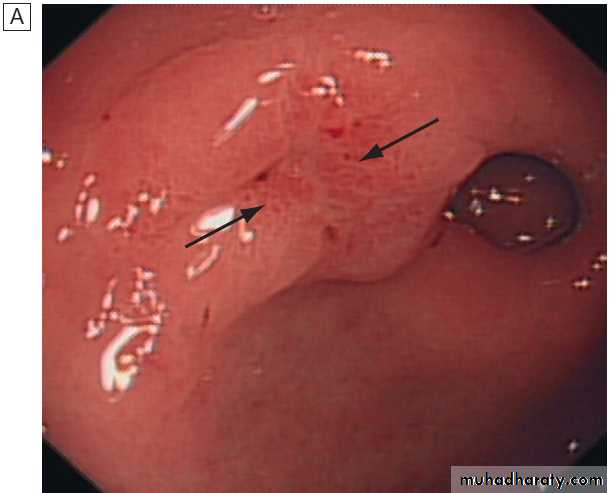

stratification in acute upper GI bleedingMajor stigmata of recent haemorrhage and endoscopic treatment. A Active arterial spurting from a gastric ulcer. An endoscopic

clip is about to be placed on the bleeding vessel. When associated with shock, 80% of cases will continue to bleed or rebleed.

B ‘Visible vessel’ (arrow).

In reality, this is a pseudoaneurysm of the feeding artery seen here in a pre-pyloric peptic ulcer. It carries a 50% chance of rebleeding.